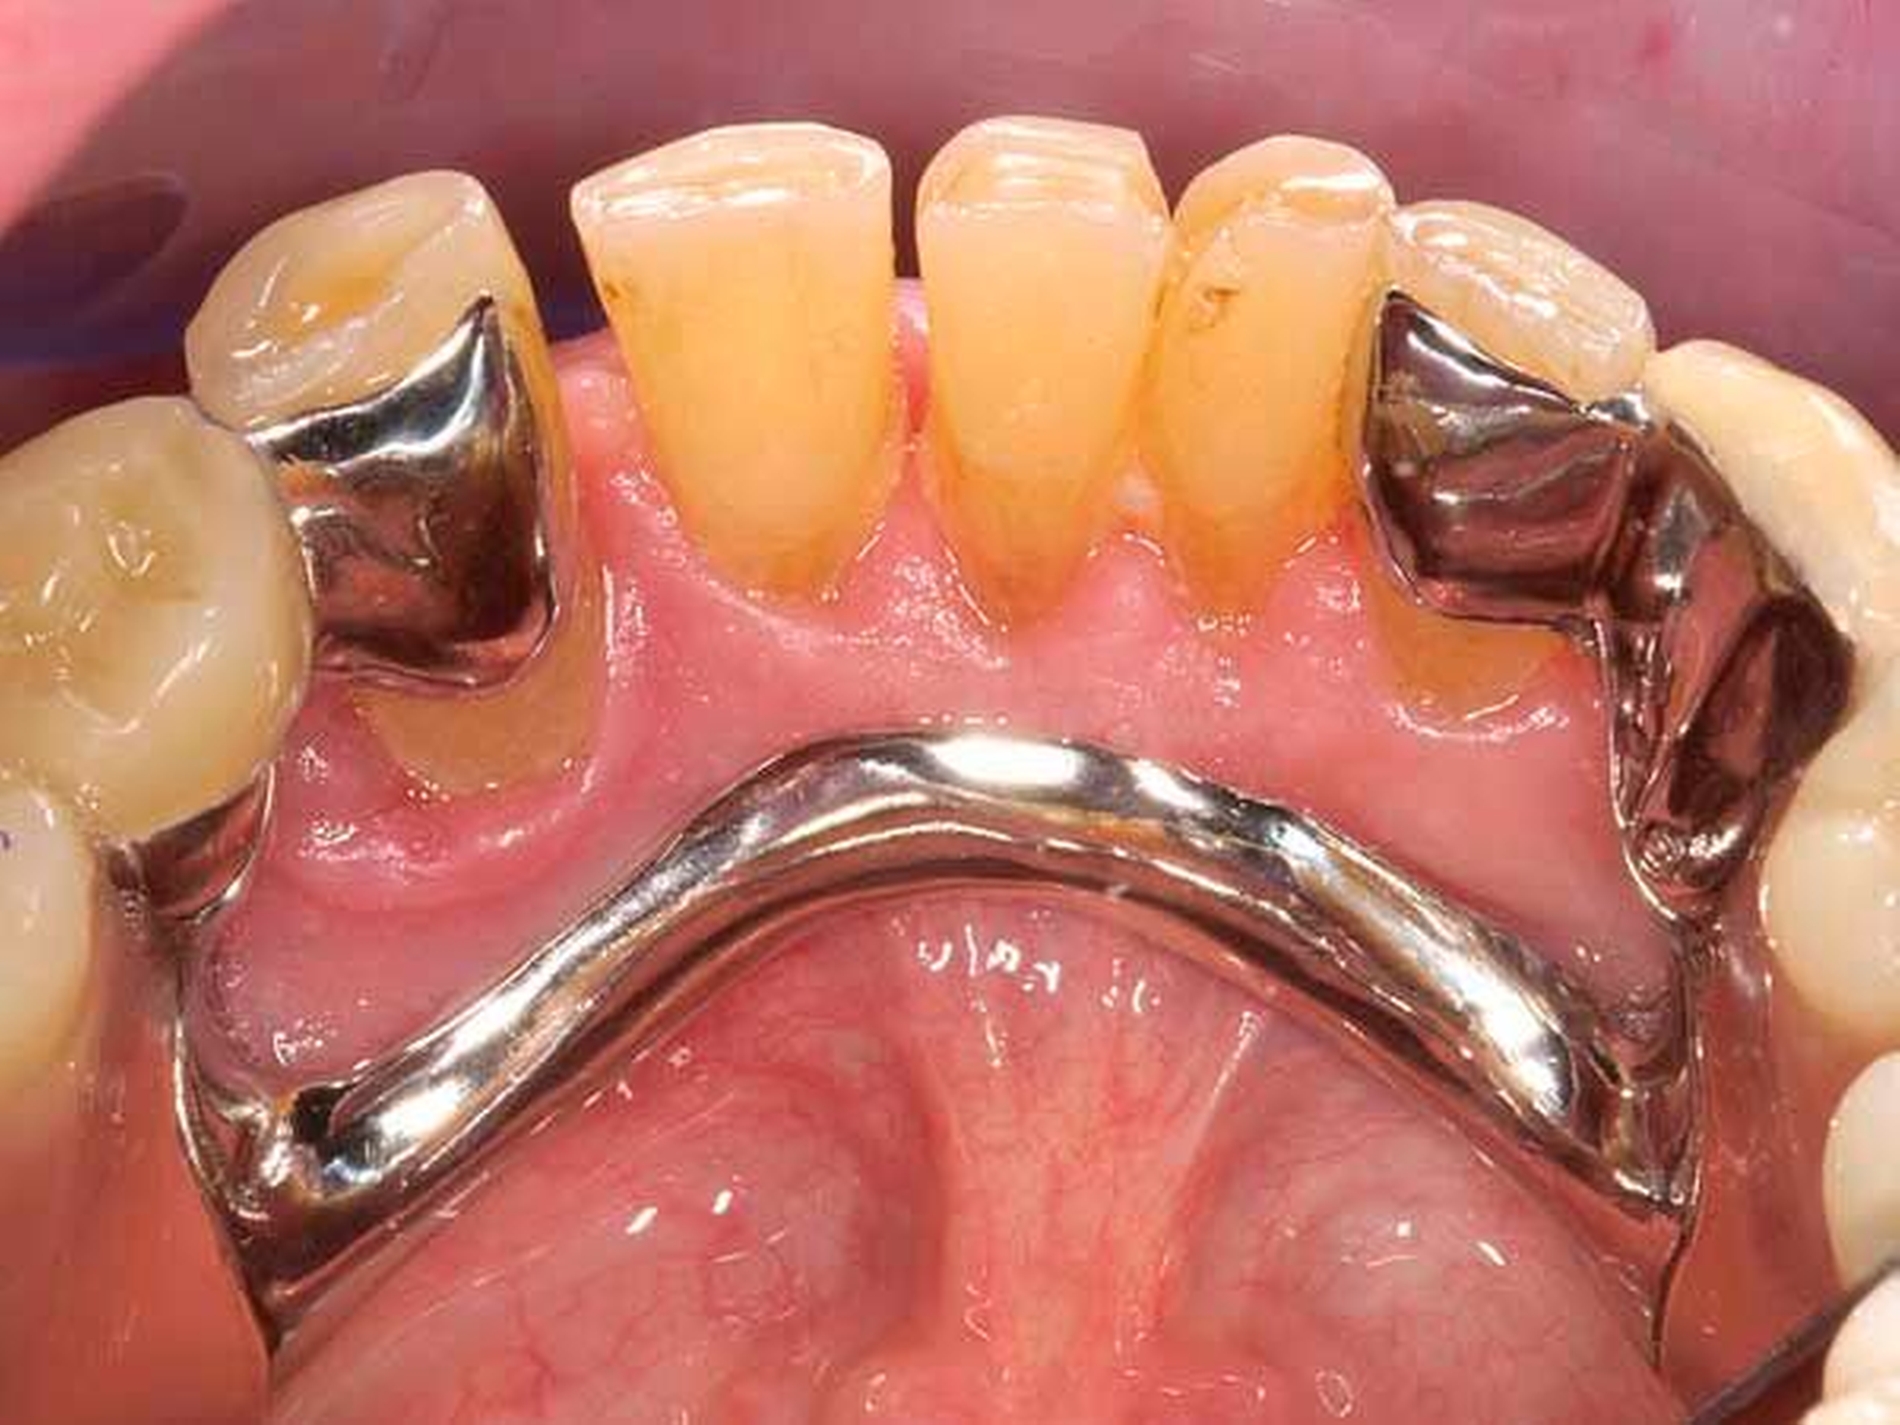

Das Orthopantomogramm (Abbildung 7) zeigt die Gebisssituation eines 89-jährigen Patienten mit kardiovaskulärer Anamnese (Herzinfarkt, Stent-Implantate) und deutlich reduziertem, fast hinfälligem Allgemeinzustand. Der Patient erhält 14(!) verschiedene Medikationen. Der überweisenden Kollegin erschien die Behandlung in der Praxis zu riskant. Nach Abschluss der Extraktionstherapie stellte sich der Patient zur prothetischen Beratung und Weiterversorgung an unserer Poliklinik vor. Im Oberkiefer wurde ein totaler Zahnersatz geplant. Im Unterkiefer verblieb ein karies- und füllungsfreies Restgebiss von 33 nach 42 (Abbildung 8). Aus gesundheitlichen Gründen schied eine Präparation der karies- und füllungsfreien Zähne für die Aufnahme von Doppelkronen oder metallkeramischen Kronen mit oralen Fräsungen aus.

Front- und Eckzähne sind aufgrund ihrer Anatomie grundsätzlich schlecht für die Aufnahme von Gussklammern geeignet. Die Lösung in diesem zweiten Fall bestand in der Anwendung zweier geteilter Klammern (Roach-Klammer), ausgeführt als Druckanker (Abbildungen 9 und 10). Lingual wurden die Zähne 33 und 42 mit den oralen Klammerarmen großflächig von disto- nach mesioapproximal gefasst. Gegebenenfalls müssen, nach Augenmaß senkrecht zur Einschubrichtung, die Tuberculi und der distoapproximale Kontaktpunkt im Schmelz mit einem Diamantfinierer leicht abgeflacht werden. Die Präparation für die orale Klammerauflage in Höhe der Tuberculi muss konsequent als Stufe von 1 mm Tiefe parallel zur Okklusionsebene eingeschliffen werden. Die Auflage selbst ist in den oralen Klammerarm integriert. Die vestibulären Retentionsarme liegen dem Zahn nicht passiv an, sondern stehen unter Vorspannung und drücken den Ankerzahn bei eingegliedertem Zahnersatz aktiv gegen das starre Widerlager der oralen Umfassung. Dies sichert in Verbindung mit der weiten, fast geschiebeartigen oralen Fassung und der integrierten Klammerauflage eine akzeptable Kippmeiderfunktion.

Die großflächigen Umfassungen der oralen Ankerzahnflächen erhöhen das Kariesrisiko, dem kann mit adäquater Mundhygiene und Fluoridierung begegnet werden. Zur Optimierung der parodontalen Hygienefähigkeit wurden die Regeln der „Grenzraumgestaltung nach Marxkors“ (brückenzwischengliedartige Gestaltung des ersten Prothesenzahnes mit metallischer Basis, Durchspülbarkeit, Insertion des sublingualen Bügels in den Sattel eine Prämolarenbreite hinter dem endständigen Zahn [Marxkors, 2007]) konsequent umgesetzt (Abbildungen 11 und 12).